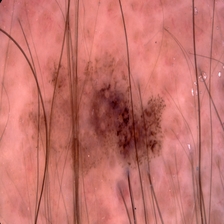

malignant

231.jpg

37 KiB

224x224px